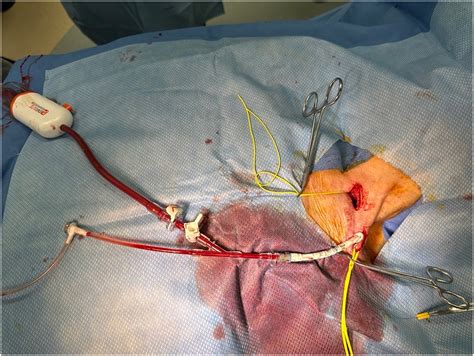

The success of Transcarotid Artery Revascularization lies in its precise clinical workflow. First, the patient is placed under light anesthesia. A small incision is made just above the collarbone. The surgeon places a specialized sheath directly into the carotid artery. The system is then connected to a flow reversal circuit, which safely diverts blood away from the brain and into a filter, which traps any loose particles. After the stent is securely placed and the artery is verified to be open and clear, the flow is returned to its normal path, and the small incision is closed.

The technical precision required for this procedure means it is performed by highly trained vascular surgeons. The ability to monitor the brain’s blood supply in real-time provides surgeons with peace of mind and patients with a higher degree of safety compared to procedures that don't employ flow reversal.